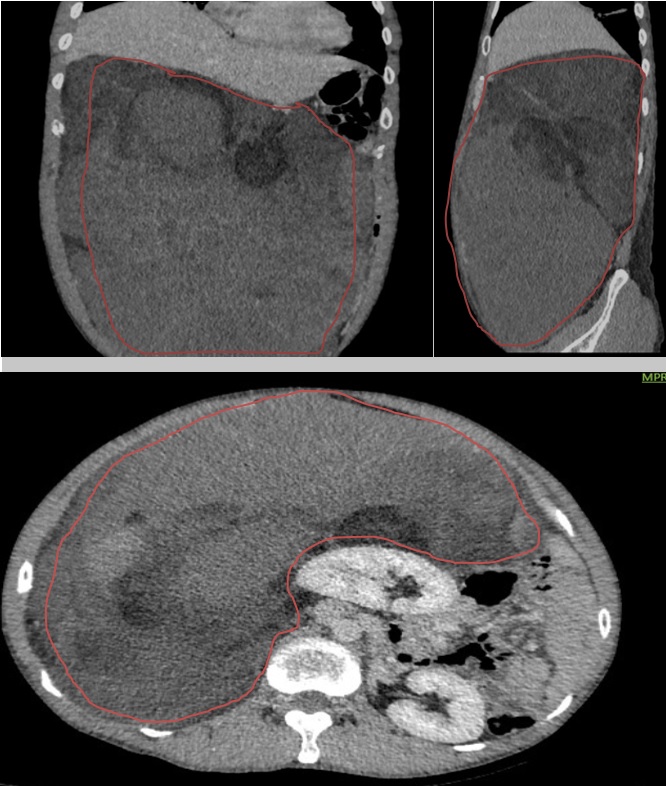

– CTscanner ổ bụng: Phát triển từ khoang sau phúc mạc bên phải có khối lớn kích thước khoảng 253x127mm, tỷ trọng hỗn hợp gồm phần đặc ngấm thuốc sau tiêm, thành phần nang dịch, mỡ và các ổ tăng tỷ trọng tự nhiên trước tiêm dạng máu cục lớn nhất kích thước khoảng 83×64 mm theo dõi liposarcoma. Khối lớn đẩy thận phải ra trước, sang trái sát đường giữa, đẩy nhu mô gan lên trên và đẩy các quai ruột trong ổ bụng sang trái. Không ghi nhận tổn thương ở các cơ quan khác.

Hình 2. Hình ảnh chụp cắt lớp vi tính ổ bụng: Khối khoang sau phúc mạc – Theo dõi Liposarcoma (vòng tròn màu đỏ)